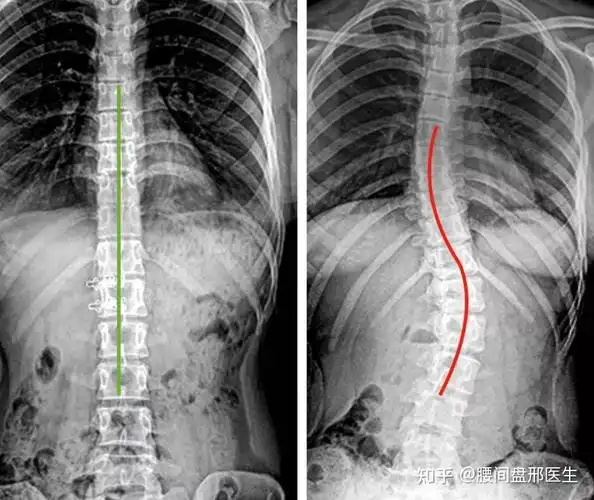

家长慌了央视发声中国中小学生脊柱侧弯人数已超500万赶紧来查